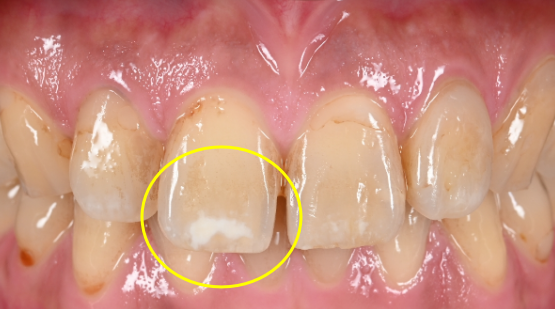

上の写真にある歯の表面の白い模様のようなものをホワイトスポットといいます。

今回ご紹介する患者様は、前歯の白い模様(ホワイトスポット)が気になるということで来院されました。